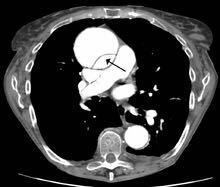

2、增强CT:常用手段。安全、简单、准确,有诊断和术前评估价值。